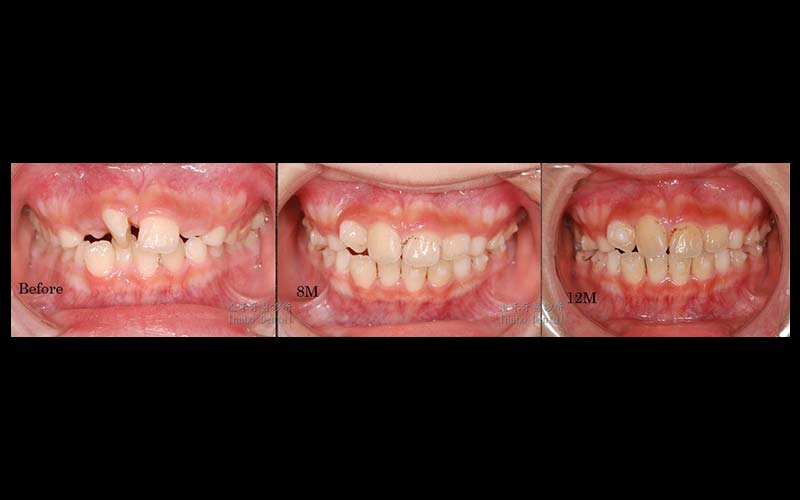

年齡:8歲

媽媽希望提早改善他牙齒凌亂不整齊,因門牙不易咀嚼食物,配戴了隱適美矯正器後,漸漸讓牙齒變整齊了,食慾也變好了。在黃金時期改善咬合不正,讓學童在生長發育的過程中可以更順利。

目前已矯正12個月